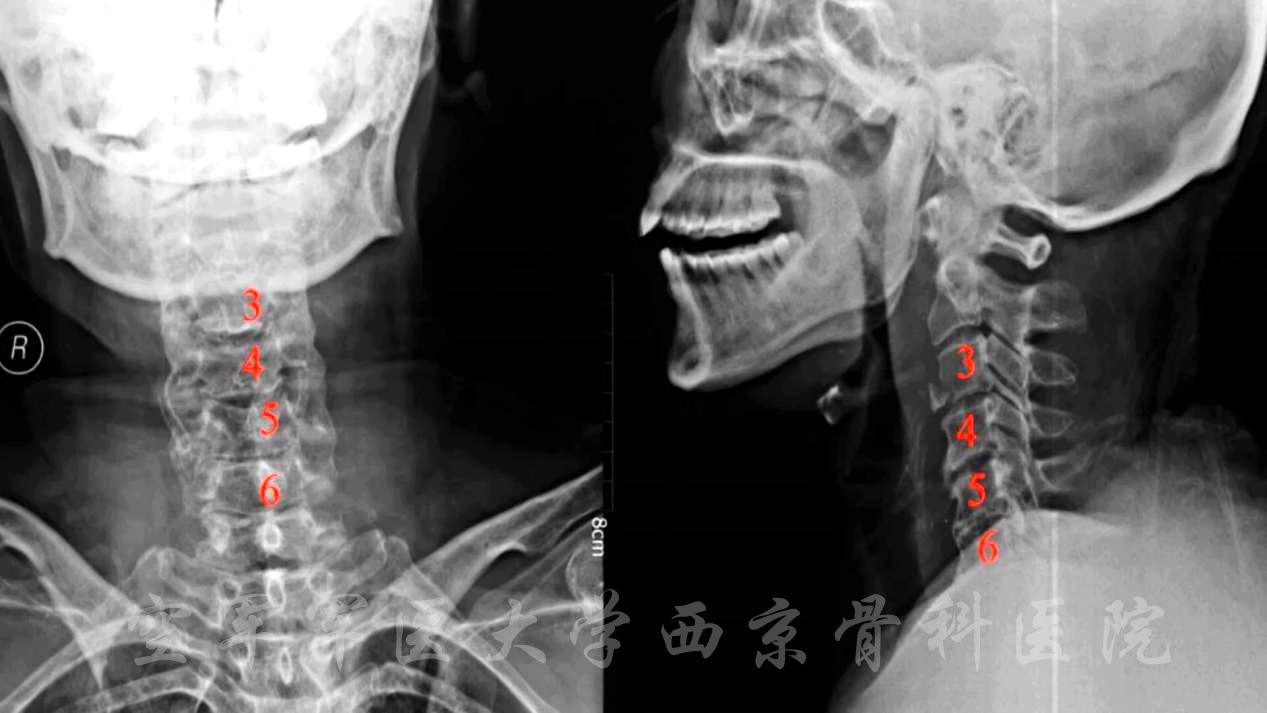

颈椎后路椎板切除减压,C3-6侧块螺钉、C2椎弓根螺钉固定,植骨融合手术

术前X线正侧位片

术前CT